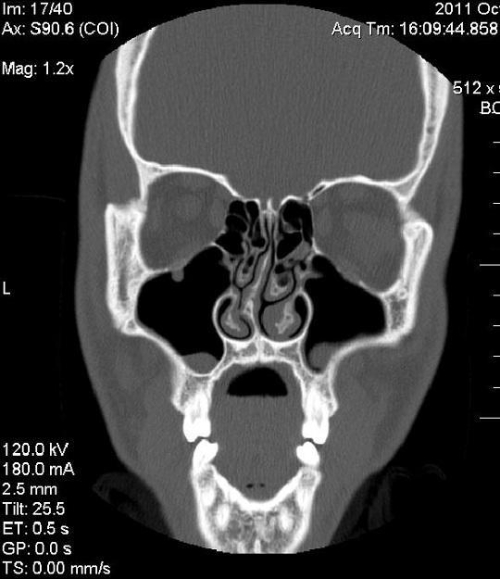

ΕΝΔΟΣΚΟΠΙΚΗ ΧΕΙΡΟΥΡΓΙΚΗ ΡΙΝΟΣ – ΠΑΡΡΙΝΙΩΝ

ΧΕΙΡΟΥΡΓΙΚΗ ΡΙΝΙΚΟΥ ΔΙΑΦΡΑΓΜΑΤΟΣ

ΧΕΙΡΟΥΡΓΙΚΗ ΡΙΝΙΚΩΝ ΚΟΓΧΩΝ